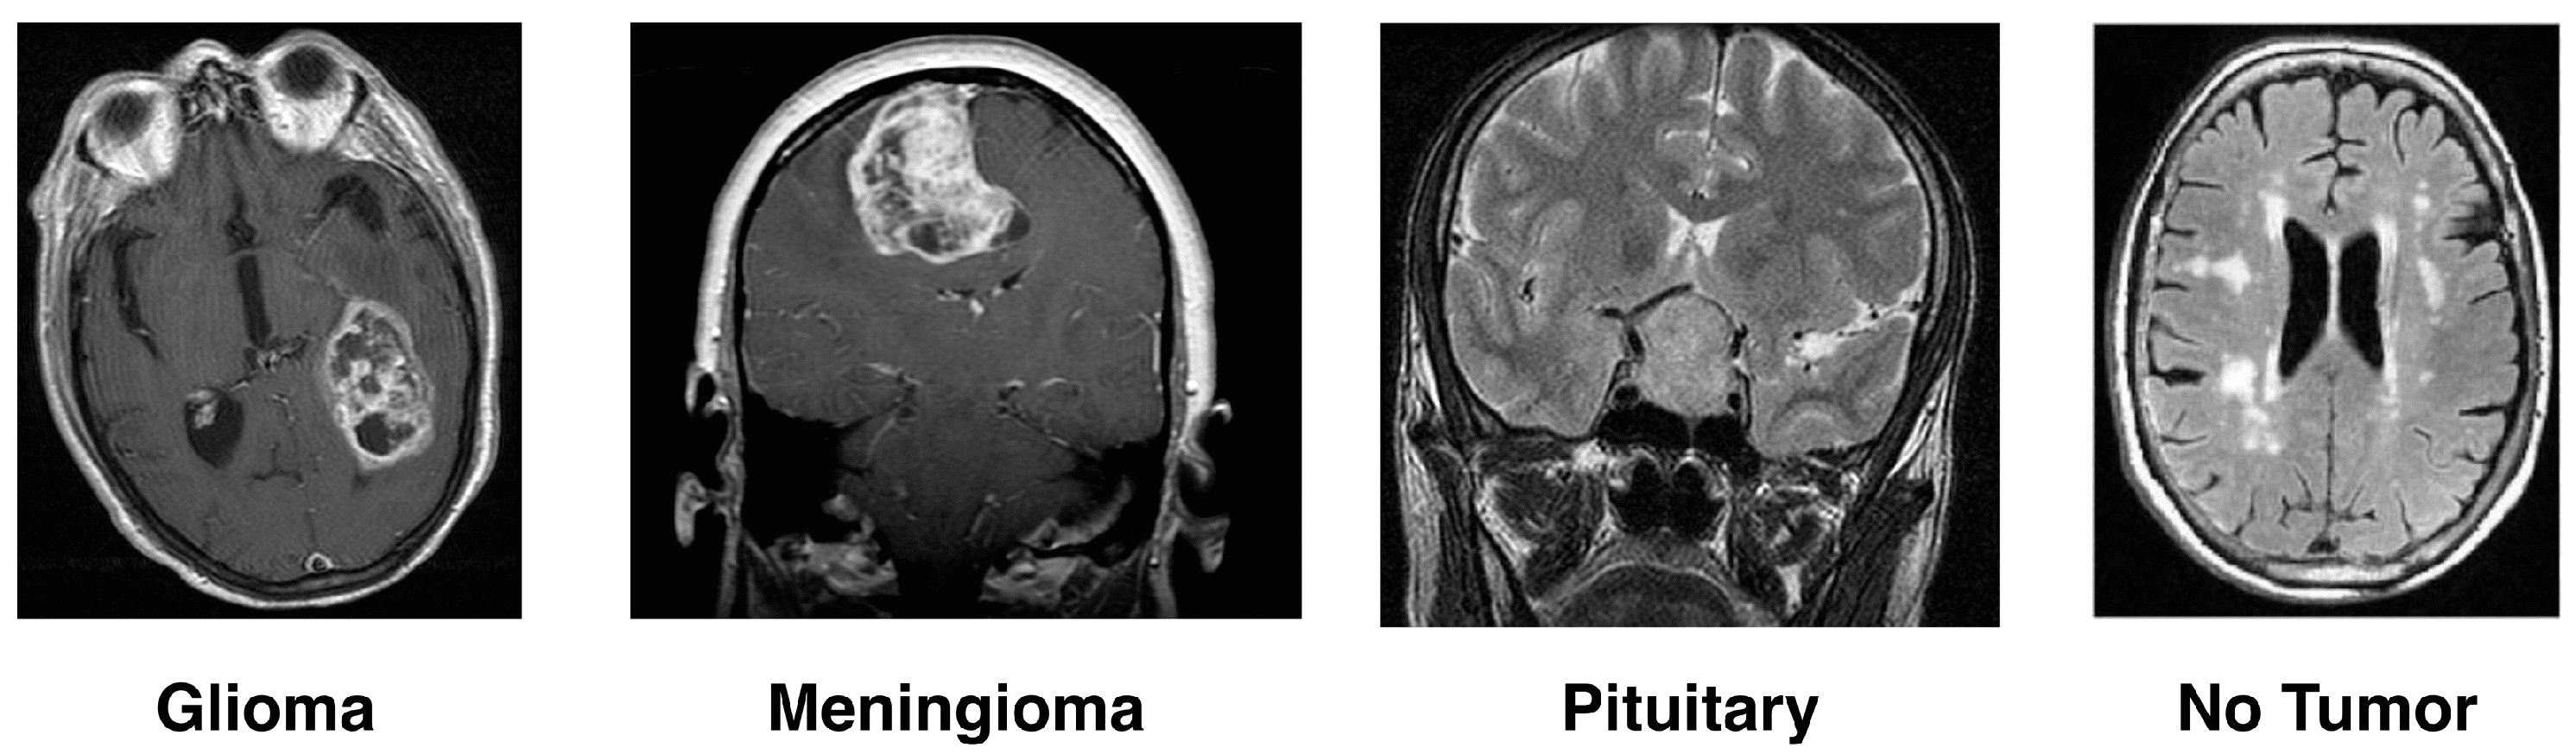

- Gliomas: One type of malignant brain tumor arises from the glial cells that help nourish and protect the brain’s sensory neurons. Glial cells are categorized according to the kind and graded into four grades by the World Health Organization (WHO). Glioblastoma multiforme (GBM) is the most fatal, and Grade IV gliomas have a poor prognosis [14,15].

- Meningioma: These are the membranes that wrap over and around a person’s brain, as well as surrounding their spinal cord, where most benign meningioma tumors usually start. They grow and pressure the brain and other nearby structures, which can cause serious health problems, even if benign. The answer to the problems, usually with surgery well removed, is how recurrence occurs [16].

- Pituitary Tumor: The pituitary gland controls the level of hormones in the body, and these tumors develop there. The vast majority of pituitary tumors (adenomas) are benign but can cause symptoms such as hormonal imbalances. Most often, the treatment involves radiation therapy, surgery, and drugs to control hormone levels [17].

- No-Tumor: Another category of MRI images is harmful, meaning they show tumors. These scans are even used as a benchmark in some research to differentiate between diseased and healthy states. It is necessary to detect and confirm that a tumor is absent for an accurate diagnosis or treatment plan.